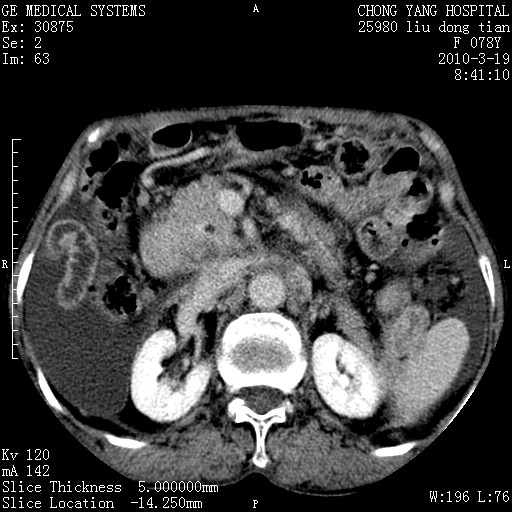

标题: CT25199:F 78Y 腹胀半年 消瘦乏力 [打印本页]

胆囊壁增厚并明显强化,胆囊癌伴多发转移瘤可能性大,淋巴瘤不除外,右肾囊肿,胸腹水.

考虑nhl,肝、脾、腹膜腔及腹膜后多发淋巴结受侵,腹水,右肾囊肿,慢性胆囊炎,右侧少量胸腔积液。

首先考虑恶性淋巴瘤 。

胰头有肿块形成,胰头ca伴肝脾、腹膜腹膜后转移

胆囊有软组织影有强化,支持胆囊癌,肝脾、腹膜后淋巴结转移。

nhl的淋巴结多围绕主动脉,而且主动脉会移位,所以不考虑nhl。

分开来讲:肝左叶、尾叶病灶有不均强化像肝癌;

脾脏病灶无强化,像多发囊肿或淋巴管瘤,不除外淋巴瘤(低强化);

胆囊增生性病变:胆囊癌,腺肌增生症,慢性胆囊炎;

肝门、胰腺头、腹膜后多个团块: 淋巴瘤,转移;

腔静脉肝内段细小有无布加可能?

一元论最好了 淋巴瘤所致改变; 胆囊癌转移不像,胆囊周围肝组织清晰,肝癌淋巴结转移?三元论都不止。

胰头ca伴肝脾、腹膜腹膜后转移!

最后报的胰头癌多发转移,脾脏单独考虑囊肿或淋巴管瘤。